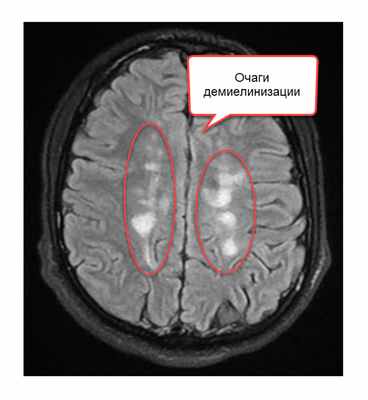

Признаки рассеянного склероза на МРТ головного мозга манифестируют себя следующим образом:

- появлением новых очагов и увеличением старых;

- во время обострения проведение МРТ головы с контрастом будет приводить к тому, что очаги демиелинизации будут накапливать контраст причудливым кольцевым способом.

Как распознают рассеянный синдром на снимках? При рассеянном склерозе на снимках заметно характерно типичное распределение очагов в белом веществе головного мозга. Кроме того, для данного диагноза характерно поражение мозолистого тела, дугообразных волокон, височных долей, мозгового ствола, мозжечка и спинного мозга. Такое распределение очагов нехарактерно для иных патологических процессов, поэтому трудностей при постановке диагноза обычно не возникает. При ангиопатии возможны поражения ствола мозга, однако они обычно симметричны и располагаются центрально, в то время как очаги при рассеянном склерозе локализованы по периферии.

В методе магнитно-резонансной томографии, исходя из названия, применяется иная физическая основа. Кратко опишем этот метод. Итак, из школьного курса физики мы знаем, что существует магнитное поле. Оно есть у всех тел в природе: у нашей Земли, у нашего с Вами тела, у каждого атома нашего тела. Поэтому к каждому телу можно пририсовать стрелку, показывающую направление магнитного поля. Если к атому прилагается внешнее магнитное поле, более сильное, чем у атома, то магнитное поле атома стремится выстроиться вдоль внешнего магнитного поля, параллельно ему. Насколько быстро и насколько точно встанет стрелка магнитного поля атома зависит от свойств самого атома: одни атомы выстраиваются быстро и ровно по направлению внешнего поля, другие с отклонением и медленно. В магнитно-резонансном томографе подается мощнейшее магнитное поле, чаще всего его напряженность составляет 1,5 Тл. К примеру, магнитное поле всей Земли составляет 0,00005 Тл. Магнитно-резонансный томограф представляет собой очень большой магнит, в центре которого напряженность магнитного поля наибольшая. Вас кладут на кушетку, затем кушетка начинает двигаться к центру магнита, похожего на трубу. Когда Вы достигаете центра магнита, то начинается процесс исследования. Магнитные поля всех атомов Вашего тела выстраиваются вдоль поля большого магнита (все маленькие стрелки встают параллельно большой стрелке). Затем перепендикулярно к основному полю магнита подается кратковременный импульс другого сильного поля. Это приводит к наклону всех маленьких стрелок атомов Вашего тела – они выстраиваются уже вдоль этого кратковременного, но очень сильного магнитного поля. Грубо говоря, все магнитные оси атомов ложатся на бок. Когда действие импульса заканчивается, магнитные стрелки атомов вновь возвращаются в положение вдоль направления магнитного поля основного магнита (вдоль трубы). Так вот, скорость возврата магнитных осей из положения на боку в вертикальное положение у разных атомов различно. У атомов водорода оно одно, у атомов кислорода другое, у атомов меди третье, у атомов железа четвертое. А так как каждый участок тела, каждый участок головного мозга состоит из разного количества разных атомов, то и возврат атомов к вертикальному положению осей будет от каждого микроскопического участка головного мозга разным. Существует два основных вида изображений: T1-взвешенное и T2-взвешенное. На Т1-взвешенном изображении фиксируется скорость возврата атомов из положения на боку в вертикальное положение. На Т2-взвешенном изображении время удержания атомов в положении на боку после кратковременного перпендикулярного импульса. Компьютерная программа обрабатывает микроскопические участки мозга по этим параметрам и формирует изображение. Участки демиелинизации существенно отличаются по количеству и спектру атомов от здоровой ткани и видны на Т2-взвешенном изображении в виде белых очагов.

- перивентрикулярно (в области, примыкающей к желудочкам головного мозга) более 3-х очагов